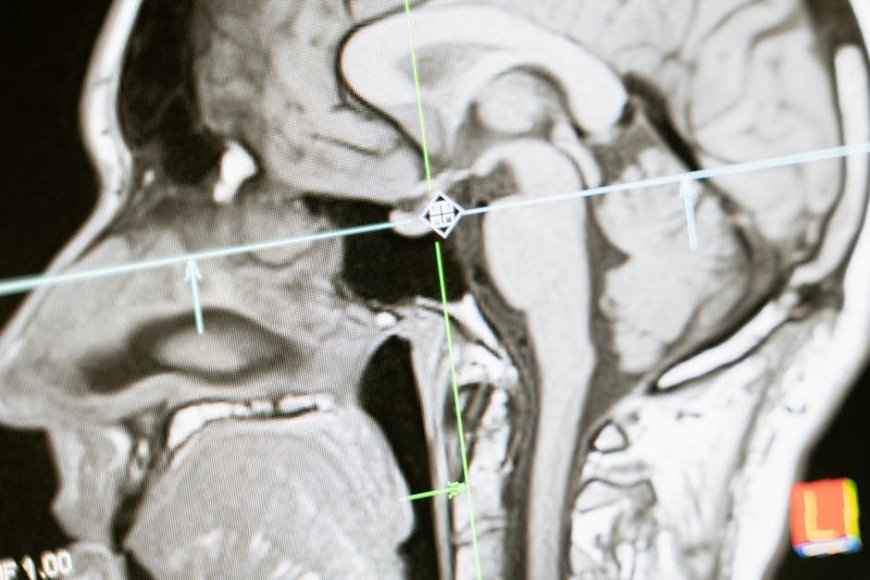

Sistem BCI Neuronano bekerja dengan merekam sinyal listrik dari otak melalui implan mikroelektroda yang ditempatkan secara bedah di korteks motorik pasien.

Sinyal-sinyal ini kemudian diterjemahkan oleh algoritma canggih menjadi perintah yang dapat mengendalikan kursor komputer, lengan robotik, atau perangkat bantu lainnya. Target utama dari perangkat BCI medis ini adalah individu yang menderita kondisi neurologis parah seperti ALS (Amyotrophic Lateral Sclerosis), cedera tulang belakang, atau stroke yang menyebabkan kelumpuhan total atau sebagian, sehingga memungkinkan mereka untuk berkomunikasi dan berinteraksi kembali dengan lingkungan mereka.